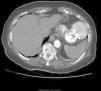

The diagnostic investigation, including computed tomography (CT) angiography (Figure 1) and left ventricular angiography (Figure 2), showed a large (52 mm×48 mm×55 mm) left ventricular wall pseudoaneurysm and a 21 mm×24 mm defect in the ventricular wall.

Figure 2.

Left ventricular angiography showing a large left ventricular wall pseudoaneurysm with a defect in the ventricular wall.